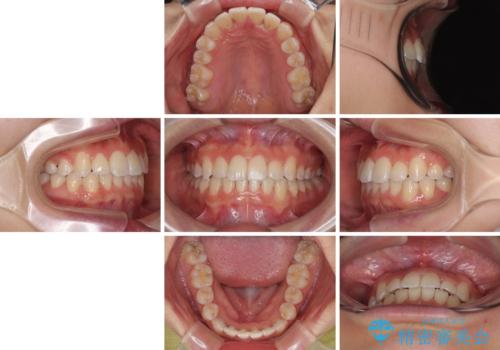

前歯のクロスバイト 裏側に隠れた歯をワイヤー装置で短期間治療

装置の外見を気にしていましたが、短期間で治療を終えることができるだろうと伝えると、安価であるメタルブラケットを選択されました。

想定通り、1年強で綺麗に仕上げることができました。